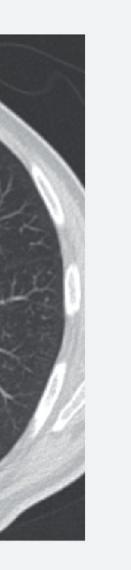

Anche la necrosi del tumore può essere considerata un marcatore predittivo di beneficio clinico. Cambiamenti della densità tumorale ed anche necrosi di lesioni polmonari sono state descritte in pazienti che ricevevano terapia antiangiogenica e vengono considerate come risposta della malattia. L’analisi post-hoc dello studio CORRECT (RadioCORRECT)14 ha mostrato che una precoce valutazione radiologica a 8 settimane è utile per predire i risultati clinici della terapia con regorafenib nei pazienti con metastasi polmonari al basale. Il 20% dei pazienti con metastasi polmonari nel braccio con regorafenib presentavano cavitazione alla CECT basale. Questi pazienti erano quelli che più verosimilmente

Figura 7. Correlazione tra HFSR e sopravvivenza nello studio osservazionale post-marketing giapponese13

hanno sviluppato un aumento della cavitazione a 8 settimane e hanno raggiunto una maggiore PFS e OS rispetto ai pazienti che non presentavano cavitazione al basale.

Figura 8. RadioCORRECT: esempio di cavitazione polmonare a 8 settimane14

Prima del trattamento con regorafenib.

Dopo il trattamento con regorafenib.